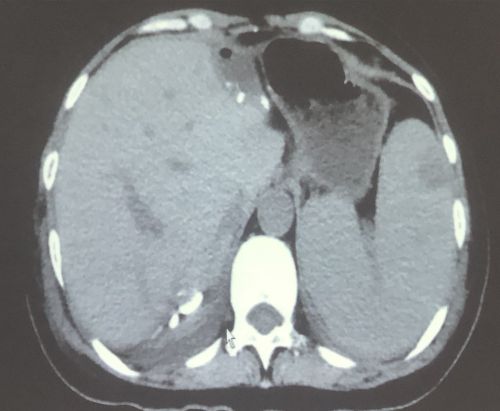

术后影像显示:肝脏转移瘤消失。